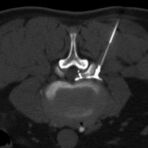

Interventionelle Eingriffe

Durchführung am Standort im Diakonissenkrankenhaus

• z. B. Punktionen zur Gewebsentnahme

Schmerztherapie

(dazu mehr auf der Seite Schmerztherapie)

Der Multislice-Scanner ermöglicht eine dem aktuellen Stand der Technik entsprechende, leitliniengerechte diagnostische Untersuchung sämtlicher Körperregionen. Darüber hinaus gestattet der neue Computertomograph auch eine für Arzt und Patient bequeme Durchführung CT-gestützter Interventionen wie z.B. Schmerztherapien der Wirbelsäule.